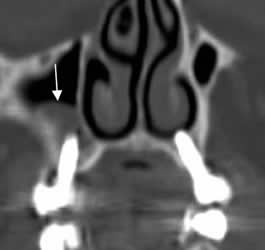

Fig 52. Sinusitis odontogénica.

TAC reconstrucción ortogonal. Engrosamiento en la mucosa del seno maxilar, por proceso inflamatorio. (Flechas gruesas). Se identifica lucencia periapical, por enfermedad periodontal asociada. (Flechas delgadas).